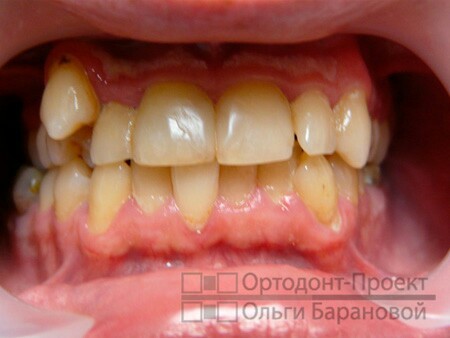

Ах да, кто интересовался фотографиями: их нет :( Ну в смысле фото "до" я не делала никогда (для меня это была не самая приятная тема), когда началось лечение мне вообще было не до того и я откровенно забыла, что есть люди интересующиеся этим. "После" делать тоже смысла нет- не самый светлый цвет, но вполне здоровый, зубы как родные, смотреть в общем не интересно, если не с чем сравнить. Было фото "забора" разве что, но туда жесть нужна явно, да и найти не могу чего-то. Еще есть снимок до установки штифтов, в середине лечения и переделки работы криворуких мудаков что занимались мной раньше. Качество какое есть, пардоньте :( Комментарии от врачей о состоянии моих зубов были в прошлом посте. Оказалось не так все дерьмово как выглядит.